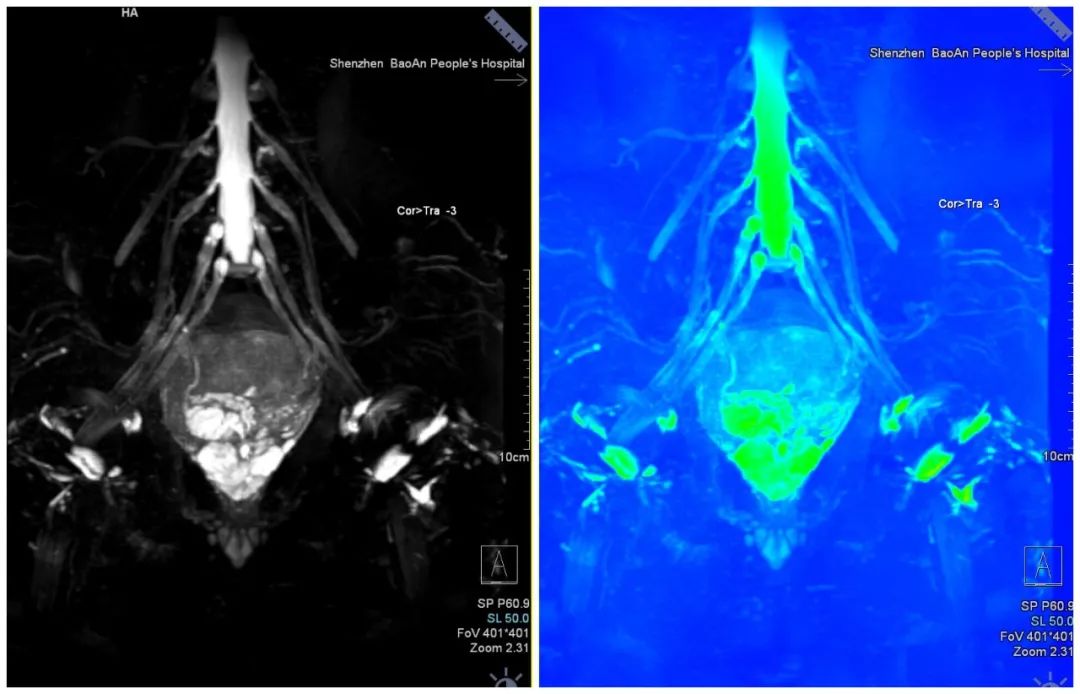

脊髓神经根成像

去金属伪影技术

全身类PET